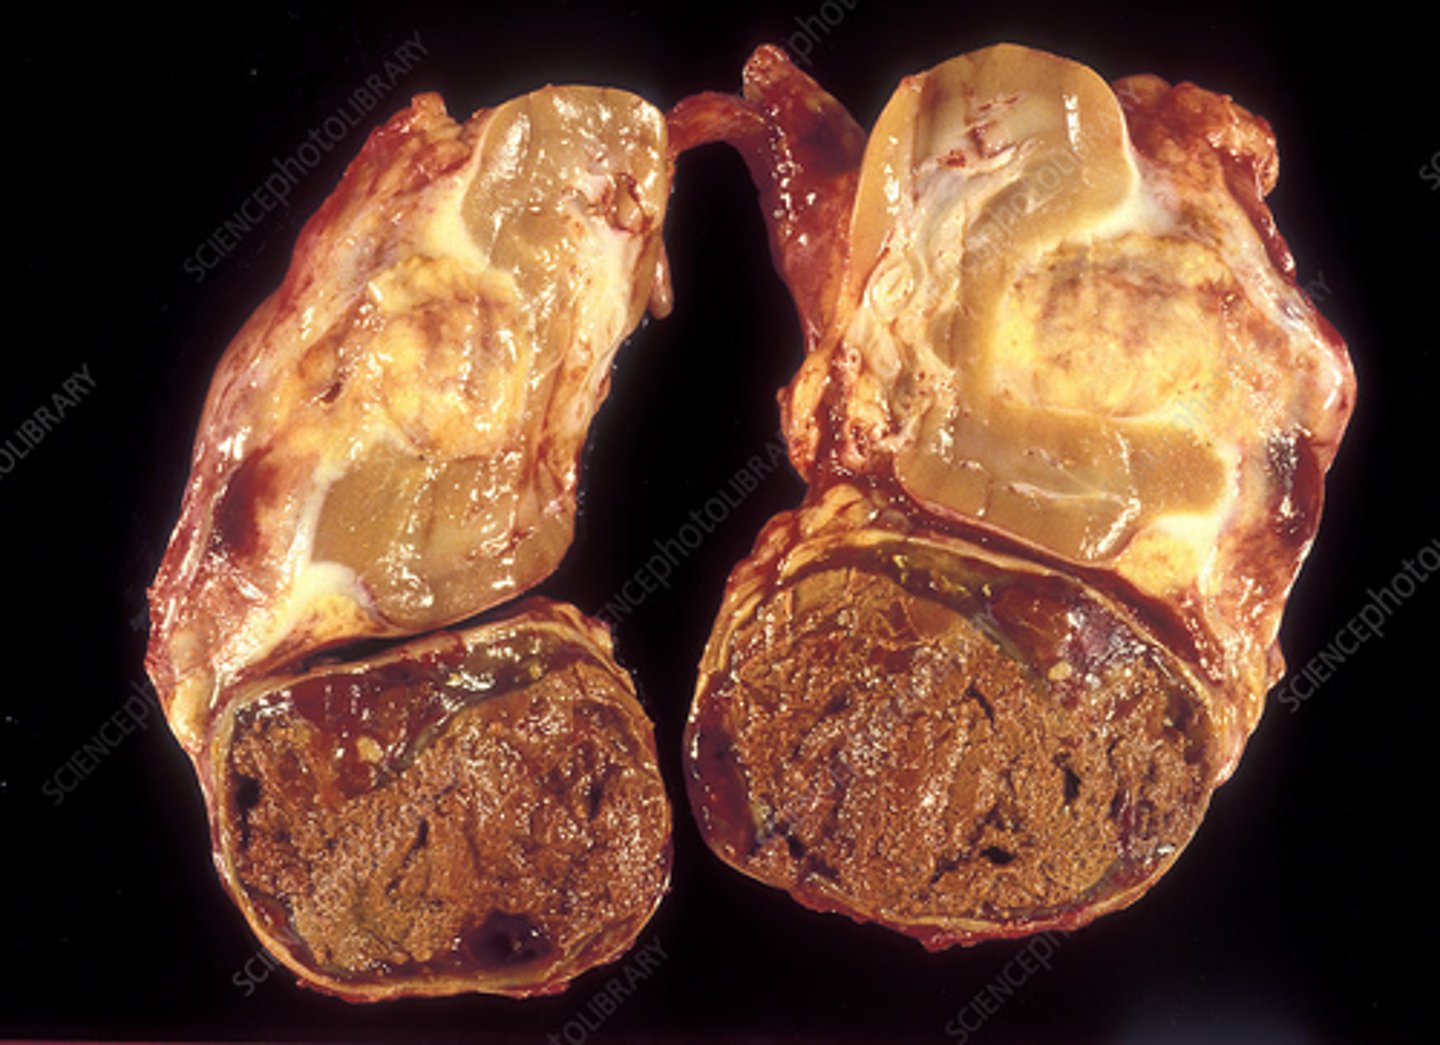

adrenal carcinoma

Pathology?